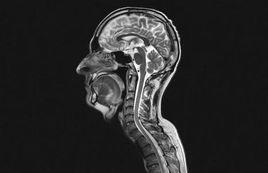

核磁共振技術主要有兩個學科分支: 核磁共振波譜(Nuclear Magnetic Resonance Spectroscopy)和 磁共振成像(Magnetic Resonance Imaging,簡稱MRI )。核磁共振波譜技術是基於化學位移理論發展起來的,主要用於測定物質的化學成分和分子結構。磁共振成像技術誕生於 1973年,它是一種無損測量技術,可以用於獲取多種物質的內部結構圖象。由於核磁共振可獲取的信息豐富,因此套用領域十分廣泛,如分析化學、生 命科學、材料檢測、石油勘探和水資源探查等等。

另一方面,醫學家們發現水分子中的氫原子可以產生核磁共振現象,利用這一現象可以獲取人體內水分子分布的信息,從而精確繪製人體內部結構,在這一理論基礎上1969年,紐約州立大學南部醫學中心的醫學博士達馬迪安通過測核磁共振的弛豫時間成功的將小鼠的癌細胞與正常組織細胞區分開來,在達馬迪安新技術的啟發下紐約州立大學石溪分校的物理學家保羅·勞特伯爾於1973年開發出了基於核磁共振現象的成像技術(MRI),並且套用他的設備成功地繪製出了一個活體蛤蜊地內部結構圖像。勞特伯爾之後,MRI技術日趨成熟,套用範圍日益廣泛,成為一項常規的醫學檢測手段,廣泛套用於帕金森氏症、多發性硬化症等腦部與脊椎病變以及癌症的治療和診斷。2003年,保羅·勞特伯爾和英國諾丁漢大學教授彼得·曼斯菲爾因為他們在核磁共振成像技術方面的貢獻獲得了當年度的諾貝爾生理學或醫學獎。

•固體NMR 和NMR成像技術:這在生命科學、生物醫學和材料學中將是至關重要的,將會在分子結構特徵和動態特徵研究方面有所突破。